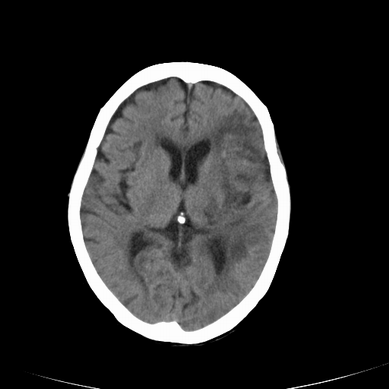

以下是引用jsgdoctor在2008-7-16 23:11:00的发言:[br]左侧大脑中动脉供血区脑梗塞